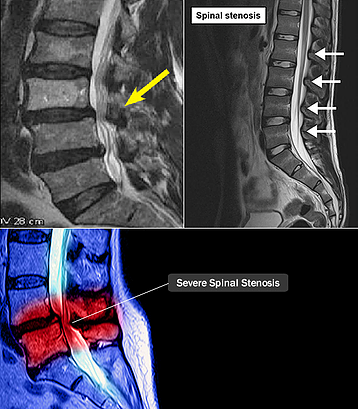

허리 협착증(요추 협착증)은 척추관이 좁아져서 신경을 압박하는 질환입니다. 척추뼈 사이의 디스크가 튀어나오거나, 척추뼈 뒤쪽의 인대가 두터워지면서 신경이 지나는 통로(척추관)가 압박되는 현상을 말합니다.

- MRI 검사: 척추관의 좁아짐, 디스크 돌출, 신경 압박 정도를 정확히 볼 수 있습니다. (가장 정확한 검사)